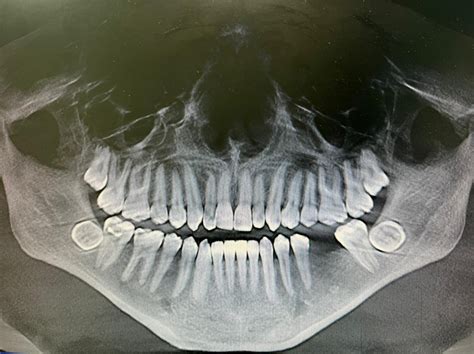

Dentists use advanced imaging to monitor the position and health of your 3rd molar teeth. During a routine exam, a panoramic X-ray is typically taken. This image provides a complete view of the upper and lower jaws, allowing the dentist to observe the angle of the teeth, their proximity to nerves, and whether they are likely to interfere with the alignment of your existing healthy teeth.